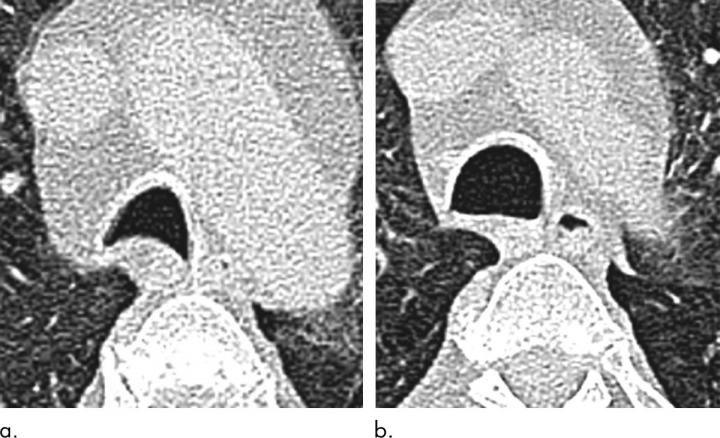

The researchers used CT to measure the size and shape of the trachea and assess air trapping, a phenomenon in which excess air remains in the lungs after exhaling, resulting in a reduction in lung function. Air trapping is an indirect sign of obstruction in the small airways of the lung.

When the researchers compared results at baseline and six months after bariatric surgery, they found that surgery and weight loss were associated with morphological, or structural, changes to the lung and trachea.

Post-surgery CT showed reductions in air trapping and a lower incidence of tracheal collapse. Change in the extent of CT air trapping was the strongest predictor of improvement in dyspnea, or shortness of breath.

"For the first time, this study has demonstrated changes in the CT morphology of large and small airways that improve when individuals lose weight," Dr. Copley said. "These features correlate with an improvement in patient symptoms."